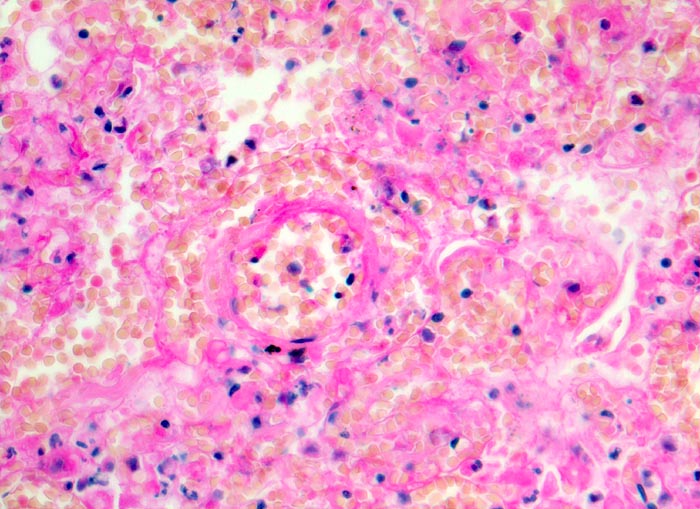

Morphologische Merkmale:

- Scharf begrenzte dreiecksförmige hämorrhagische Nekrose des Lungenparenchyms.

- Alveolen gefüllt mit zerfallenden Erythrozyten, Kerntrümmern und Fibrin.

- Lungengerüst erhalten im Randbereich der Nekrose, nicht mehr erkennbar im Zentrum.

- Abgeblasste Zellkerne in der Nekrosezone.

- Pulmonalarterienast mit nicht wandhaftendem Thrombembolus am Rand des Infarktes.

- Frischblut im Lumen des begleitenden Bronchiolus.